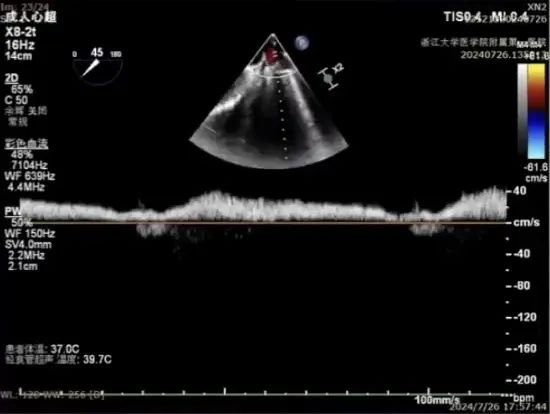

经胸超声评估

经胸超声评估显示,二尖瓣前叶脱垂,并可见广泛反流。

术前可见肺静脉逆流,术后则消失,反流明显改善。跨瓣压差由术前的19mmHg降至术后8mmHg,瓣膜血流动力学明显优化。同时,LVEDD由术前的6cm逐渐降至<5.0cm,患者左心室容量负荷减轻,心腔重构趋势明确,手术取得良好近期疗效。

术前

术后

术前

术后